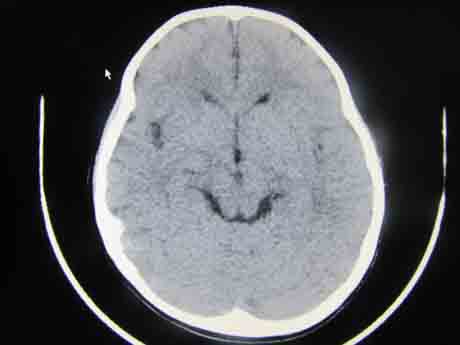

CT50602:右侧钙化诊断什么?

右侧钙化诊断什么?

右侧枕叶见弯曲的条带状钙化影,边界清,患侧颅骨骨质增厚,脑皮质萎缩,余脑实质及脑室、脑裂、脑沟均未见异常,中线结构居中。

意见:考虑颅三叉神经瘤,需与动静脉畸形鉴别,建议MRI

右侧枕叶区可见弯曲条状及点状钙化,局部脑皮质增厚,考虑颅颜面血管瘤综合症。